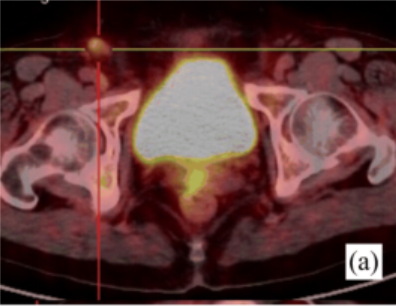

此前一位40岁的女性患者赵某某,因“发热伴皮疹1月”收入我院,患者曾于外院抗感染治疗无效,入我院后完善血常规:白细胞18.0×109/L,中性粒细胞百分比89.5%;铁蛋白4400ng/ml;血沉83mm/h;PCT0.10ng/ml;CRP82mg/L;抗核抗体谱、类风湿因子、抗“O”、肿瘤标志物、结核抗体、T-SPOT、血培养、腹部彩超等均未见异常,胸部CT提示肺部纤维灶,进一步完善骨髓穿刺、骨髓活检亦无明显异常,为明确患者发热伴皮疹原因,进一步行PET/CT检查,结果提示双侧腋窝、右侧髂外血管旁及双侧腹股沟区多发肿大淋巴结,局部淋巴结病灶FDG代谢轻度增高,考虑非特异性炎性改变。综合结合患者相关表现、检查以及排除其他病因,相关学科讨论后,初步考虑为成人still病,予以糖皮质激素治疗后皮疹消退、体温降至正常,病情平稳后带药出院。

图为患者赵女士的PET/CT融合成像显示腋窝、腹股沟淋巴结FDG摄取增高